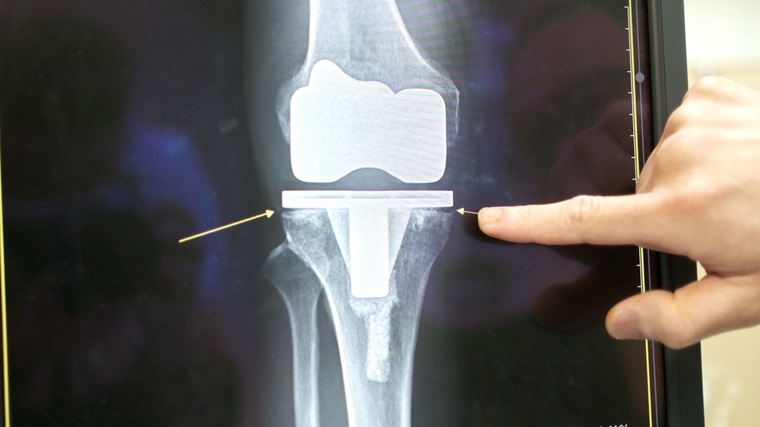

▲若以3D列印活動型骨水泥治療人工關節感染,除了能有效控制感染,還可改善關節功能。(圖/中國醫藥大學附設醫院提供)

林宗立醫師進一步分析,慢性人工膝關節感染的標準治療為2階段手術:第1階段手術為移除人工關節、並置入含抗生素的活動型骨水泥,文獻顯示,感染治療成功率因此高達 92%至95%,待感染控制後,再進行第2階段手術移除骨水泥及人工關節再置換手術,可大幅降低感染復發。林醫師說,與過去靜態型骨水泥相較(膝關節需打直無法活動且需打石膏固定),置入活動型骨水泥的膝關節活動角度大,可減少關節攣縮及肌肉萎縮,利於第2階段重建手術。

林宗立醫師說明,近年來傳統手作、翻模或市售活動型骨水泥因設計上較粗糙或力學不穩定,產生不少骨水泥相關的機械性併發症,如骨水泥破裂鬆脫或關節脫臼,導致膝關節功能反而變差、療程延長、需再接受手術並增加重建手術的困難度。林宗立醫師團隊研發的「3D列印活動型骨水泥」能顯著控制感染,改善關節功能,增加活動角度,並減少併發症。